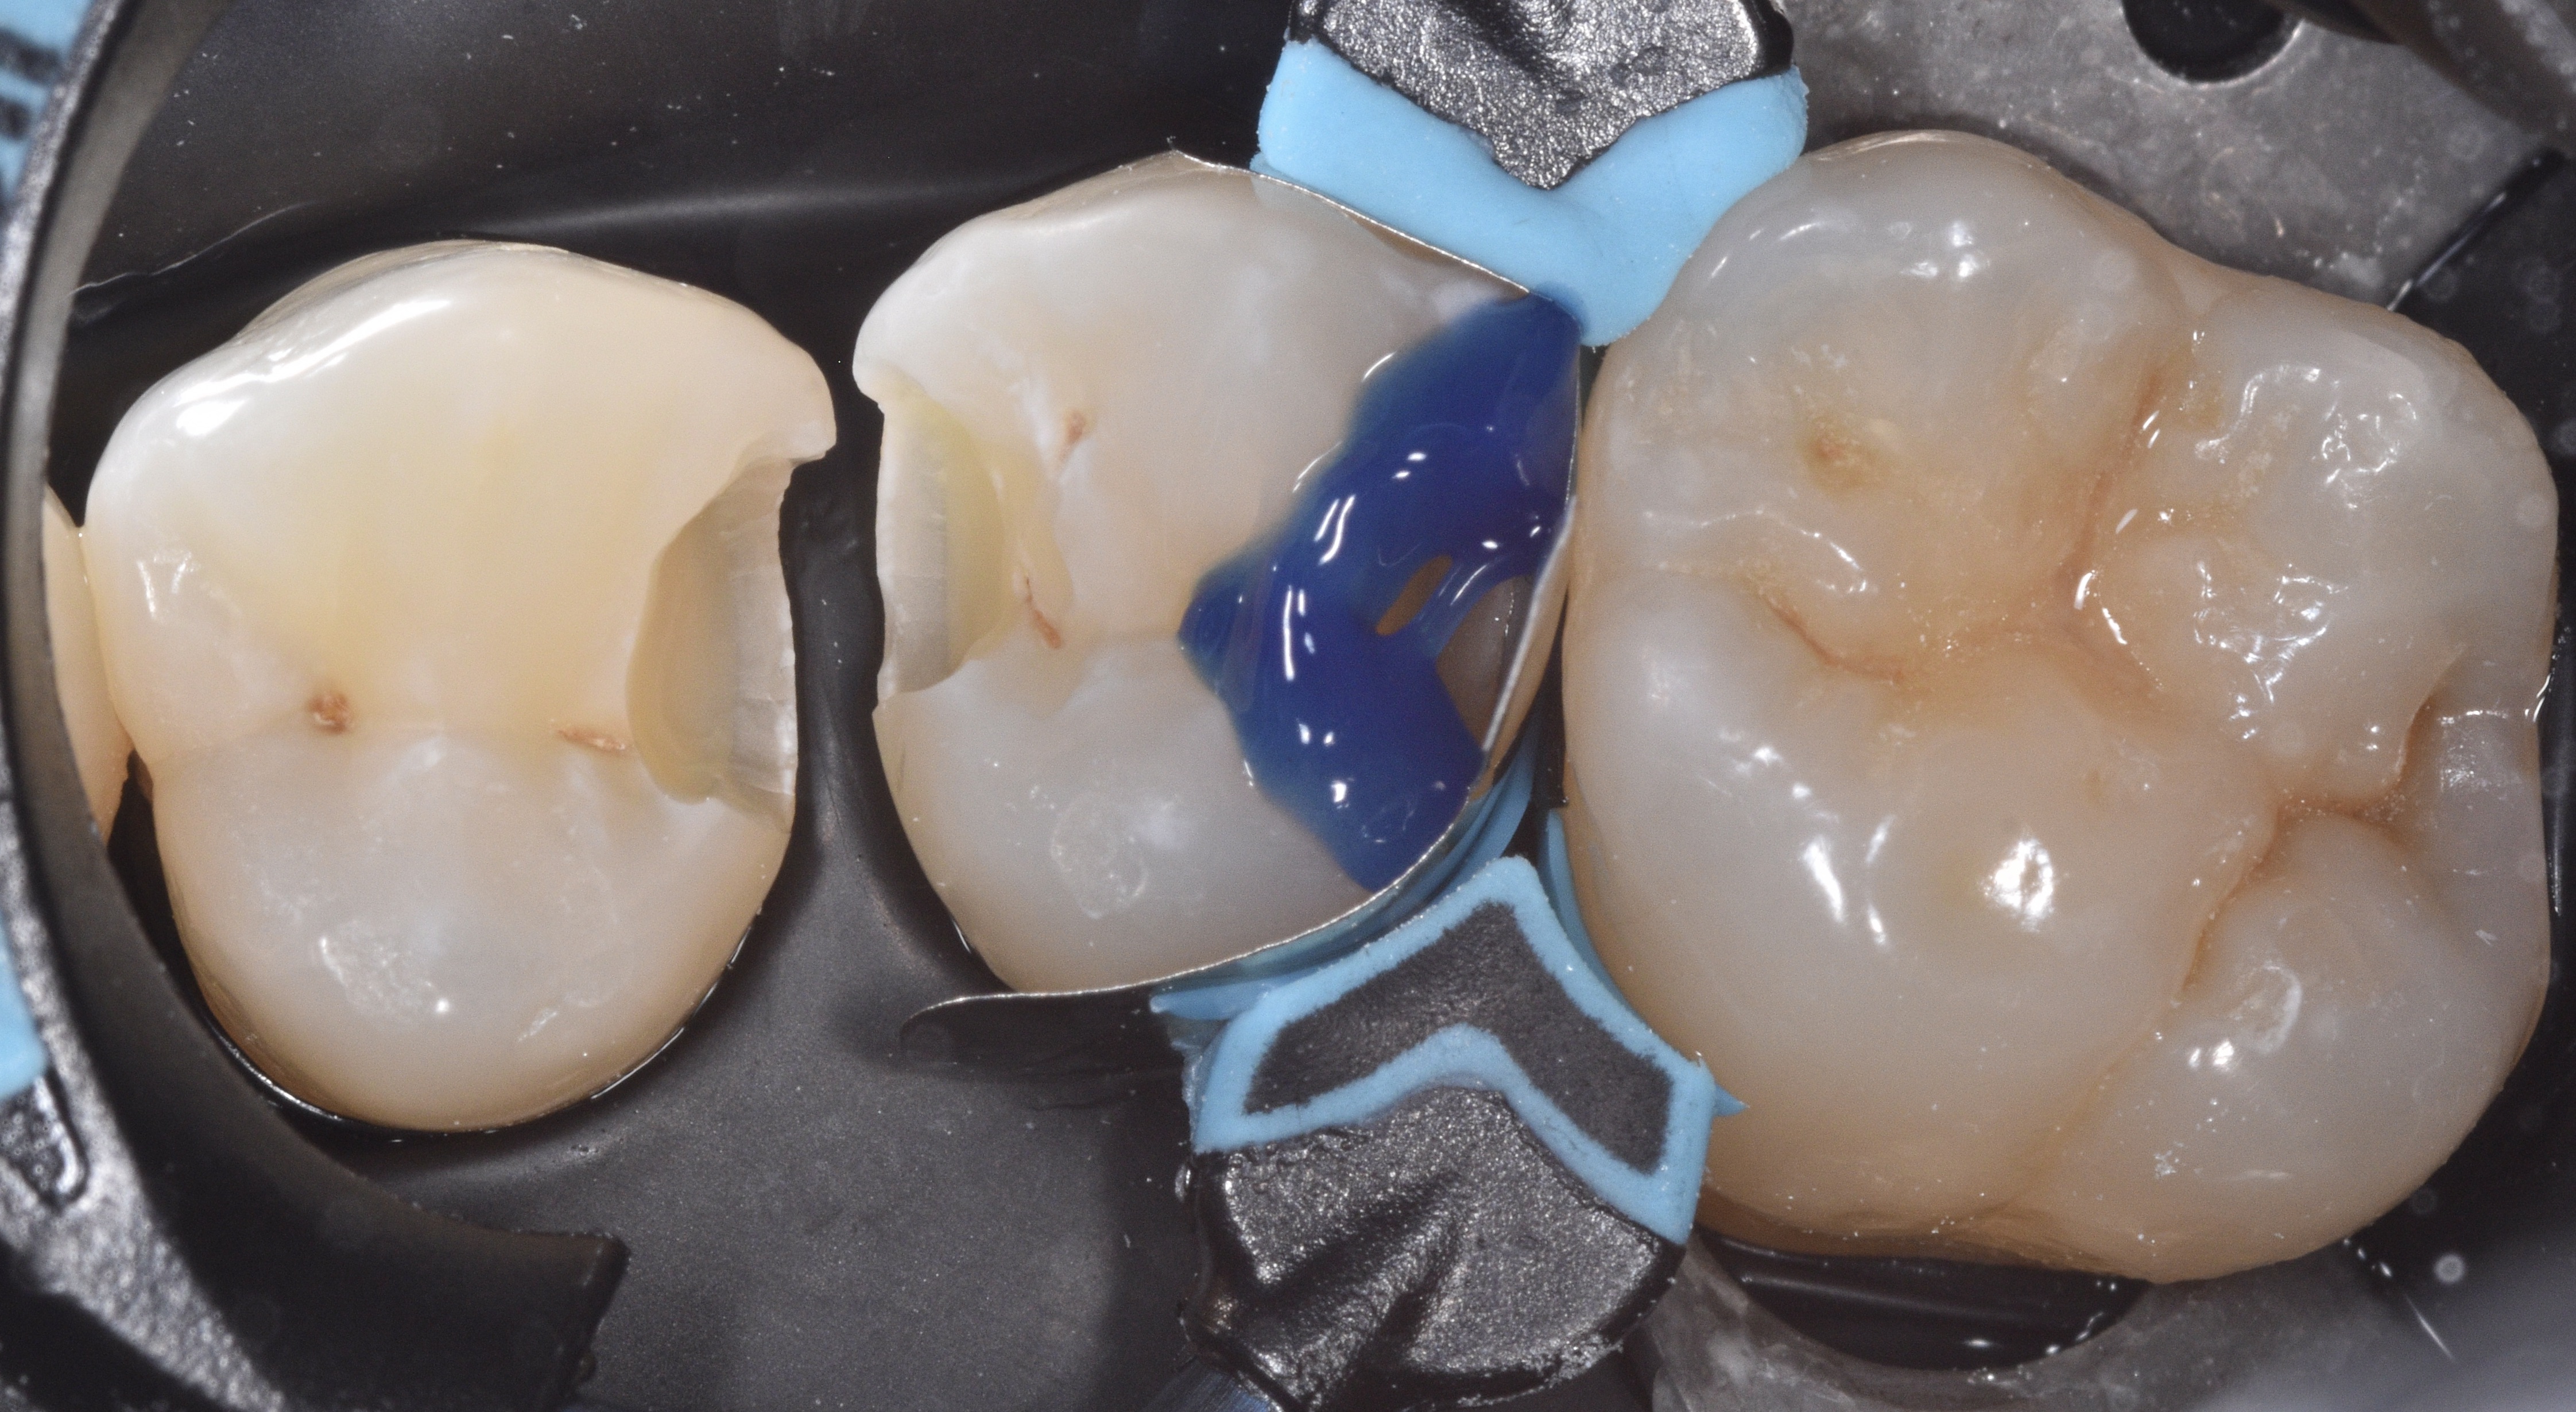

Caries was removed using a minimal intervention approach which helped with keeping the central groove area intact on tooth #13 (Figure 2). Once the infected dentin was completely removed and a clean peripheral seal zone obtained, we cleaned the preparations using 23-micron aluminum oxide combined with distilled water (AquaCare) and then moved forward with selecting the ideal matrix system for this case. Garrsion’s Quad matrix system has quickly become my preferred due to its “split” wedge systems that helps with “pushing” the band mesial, distal or both (in back-to-back cases) (Figure 3).

The Restorative procedure was initiated with #13 DO. After placing the matrix system, selective enamel etching for 15 seconds was completed, rinsed and dried (Figure 4)